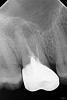

forgo314 Опубликовано 25 апреля, 2013 Поделиться Опубликовано 25 апреля, 2013 Здравствуйте!6 дней назад заболела половина зуба (вторая была вырвана 5 лет назад с корнем, т.к. отломилась) очень сильно, на зубе была коронка на штифте - цельнолитая, стояла 5 лет. Обезболили (ушло 5 ампул! обычно и одной хватает а тут боль невыносимая даже после 3-й), сняли коронку, зуб вырвали по частям (по корням - на это ушло 2 часа). Врач сказал 2ч не есть, не полоскать и ничего из лекарств не принимать. 2 дня промучилась - температура 38,5, адская боль, кровь не останавливалась 1й день 6 часов: не лила ручьем, а потихоньку подтекала, т.е. если убрать тампон - то течет прям в рот, чувствуется вкус (были выходные). В ПН пришла, сделали снимок, сказали: пить Амоксиклав, Синупрет, Кетонал, полоскать Хлоргексидином, и мазать Метрогил-Дента, а так - все хорошо, только у вас гайморит (у меня его сроду небыло). По поводу сообщения пазухи носа и рта - сказали что его нет, перфорации нет, вобщем все отлично. В результате пью и полощу 3 дня, болит половина лица, зуб болит (дергает) ужасно, хоть на стену лезь, спать невозможно, поэтому постоянно пью Кетонал - помогает только он. Прекращаю пить его - все заново... Тот сгусток, что был в лунке - гнил и вонял, потом выпал, на месте его - розовая лунка, дно - обнажившаяся желто-белая кость. Почитала в интернете откуда такие адские боли, оказалось - альвеолит, как он выглядит, и причины уже ясны... Прошла 3 очные консультации врачей, первый врач в платной клинике сказал что надо полоскать, пить антибиотики и все пройдет. Второй (в поликлинике)- что надо положить губку с лекарством в лунку и менять ее каждый день. И должно пройти. Третий сказал (из частной клиники) что надо вставить туда тампон с лекарством и менять через три дня. Кюретаж - все трое сказали что не надо, особого эффекта это не даст. У меня вопрос: неужели дествительно альвеолит - лечится так долго? это ведь, судя по всему, опасное осложнение, может развиться и остеомиелит, и т.п. - ведь уже неделю терплю адскую боль, постоянно на обезболивающих, и антибиотиках (но и у них есть свой срок применения ведь!), температура постоянно, больничный частники не дают,а говорят еще 2-3недели лечить - примерно. Это нормально? за это время ничего нового не разовьется на фоне альвеолита? Или сразу лучше в больницу в стационар, чтоб не упустить время (и что там будут делать, как лечить?)? Кто-нибудь вообще его вылечивал, и как это происходит? вопрос к врачам.Вот снимки до (с коронкой) и после Ссылка на комментарий

SergioS Опубликовано 25 апреля, 2013 Поделиться Опубликовано 25 апреля, 2013 Скорее это альвеолит. На его фоне при приеме антибиотиков вряд ли что-то может развиться. На снимке после удаления никаких инородных включений(корней нет). Кюретаж лунки все-таки я бы сделал. Это облегчит ваши страдания. Ссылка на комментарий